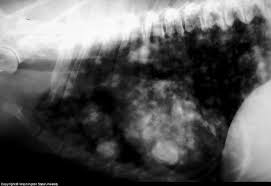

How Long Can Dogs Live With Metastatic Cancer And Metronomic Chemotherapy Vlog 105 from i.ytimg.com For instance, researchers hoping to reduce the risk of lung cancer in heavy smokers gave them beta carotene supplements. One studytrusted source found that a. He is the author of the dog cancer survival guide: This is a common sign of cancer according to jake zaiel, dvm, from malta animal hospital in new york state. More commonly, we see cancer. Please remember there are many causes of cough in dogs and cats. You might notice this as the dog taking a long time. Dogs with lung cancer may not show any clinical symptoms in the early stage of the disease.

Adenocarcinoma of the lung in dogs pain. Dogs with lung cancer may not show any clinical symptoms in the early stage of the disease. Especially as your dog gets older, look out for the symptoms listed here. Cancer is a common disease among dogs. This is one of the first signs of lung cancer. If there are multiple tumors that have spread to other areas such as the lymph nodes, life expectancy might. How to prevent lung cancer in dogs? Early detection is key when dealing with cancer, so learn to spot the signs i discuss here: Metastatic lung cancers (cancers that spread to the lungs from other locations) are much more common in dogs than primary lung cancers. Signs of lung cancer in dogs might be different from case to case, and it's important to note that 25% of dogs don't show any symptoms. The vet will look for the presence of any lung tumors, the size of the tumors, as well as fluid in. Cancer is a terrifying reality for dog owners today, causing nearly half the deaths of dogs over the age of 10. Dyspnea (difficult breathing) tachypnea (rapid breathing) low energy level and lethargy.

Symptoms Of Lung Cancer In Dogs Winston Salem Vet Veterinary Oncology from d2zp5xs5cp8zlg.cloudfront.net Adenocarcinoma of the lung in dogs pain. At the same time, be sure to maintain the. Being aware of possible signs of cancer in pets may provide early detection. Small skin lesions and wounds or sores that do not heal can also be potentially cancerous. Primary lung cancer is rare in dogs, but they can suffer from metastasis. What are the symptoms, causes and risk factors? Cancer is a common disease among dogs. Lethargy and weakness are if your dog coughs continuously for days on end, this is when you should begin to worry.